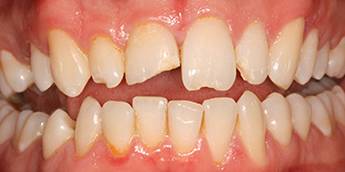

6. Eset

Nagymértékű fogkopás, erózió, csikorgatás a teljes rágóapparátust túlterhelve okoz reménytelennek tűnő helyzeteket.

Ebben az esetben implantátumok , koronák és hidak segítségével változtattunk a páciens fogainak érintkezésén. 6 hónapig ideiglenes hidakkal teszteltük a megváltoztatott harapási pozíciót. Ezután készültek el a végleges fix pótlások.